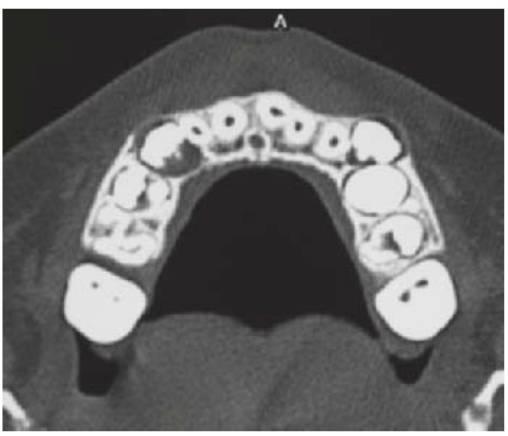

- Resulta esencial localizar la posición del diente que debe extraerse antes de la cirugía. Pueden realizarse radiografías periapicales que emplean la técnica del desplazamiento del tubo (tube-shift) para localizar el diente, pero siempre entrañan la posibilidad de errores e interpretaciones erróneas. De la misma manera, pueden utilizarse radiografías panorámicas y oclusales maxilares estándar. La proyección oclusal de vértice permite obtener una muestra más precisa de la localización horizontal y anteroposterior, por lo que es la preferida (fig. 9.8C) para ayudar a determinar el procedimiento quirúrgico óptimo. Algunos centros prefieren no utilizar esta vía debido a una excesiva radiación en el cráneo.

- Las técnicas digitales de imagen que utilizan tomografías de haz cónico proporcionan una buena definición e imágenes tridimensionales de la cabeza y el cuello y emiten mucha menos radiación que la tomografía computarizada tradicional (TC) (v. fig. 9.18 más adelante).